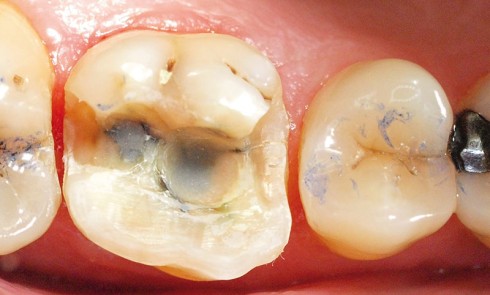

Article réservé à nos abonnés Préparations pour endocouronnes

Vrai ou faux… Question 1. La limite cervicale de l’endocouronne est réalisée sous forme d’un épaulement ou d’un congé large....